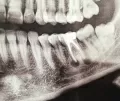

Недавно сделала рентген, на котором четко видно серое пятно в том месте, где, когда то была киста (на рентгене она была черная).

Прикрепленые фото